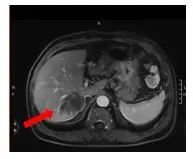

2022-03-01肝脏增强MRI(特异性对比剂):肝内多发转移瘤,大者位于肝右后叶,大小4.6*3.1cm,腹腔内仍见多发肿大淋巴结,直径1.6cm。

图6.治疗5周期后腹部增强MRI